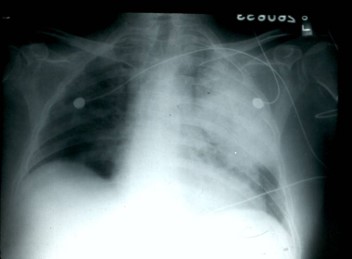

Patient A: An eleven year old asymptomatic boy who was admitted for an elective tonsillectomy.

Usually asymptomatic or accompanied by a nonproductive cough, the chest x-ray shown

in panel A is typical. The mass in the lingular segment of the left lower lobe was

suspected to be a tumor and was biopsied. Histologic examination showed numerous yeast-like

organisms with thick polysaccharide capsules on India-Ink stains. Cultures grew Cryptococcus neoformans. The mass resolved without treatment.

Lingular segment C. neoformans Left upper lobe C. neoformans pneumonia in a patient pneumonia in a normal host. with paraneoplastic Cushings syndrome.